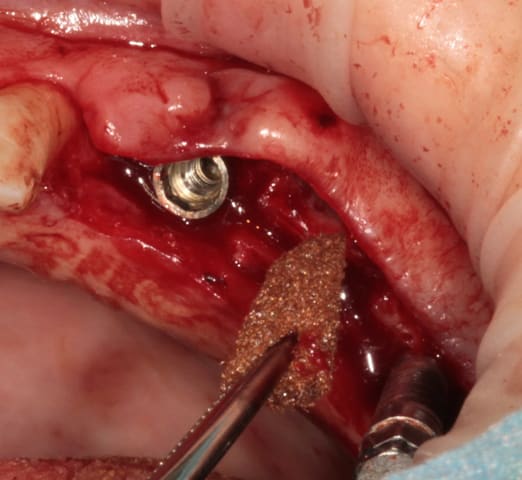

et un et deux et trois

D1 pour "assouplir"

éponge

implant lisse conique

éponge...

après les implants lisses coniques il faut passer aux lisses Axioms

donc Ostéotomes impactés pour mettre la corticale du sinus aux dimensions et pousser la membrane (et l'éponge)

en 25 pour le moment l'axiom lisse est de 3.4mm